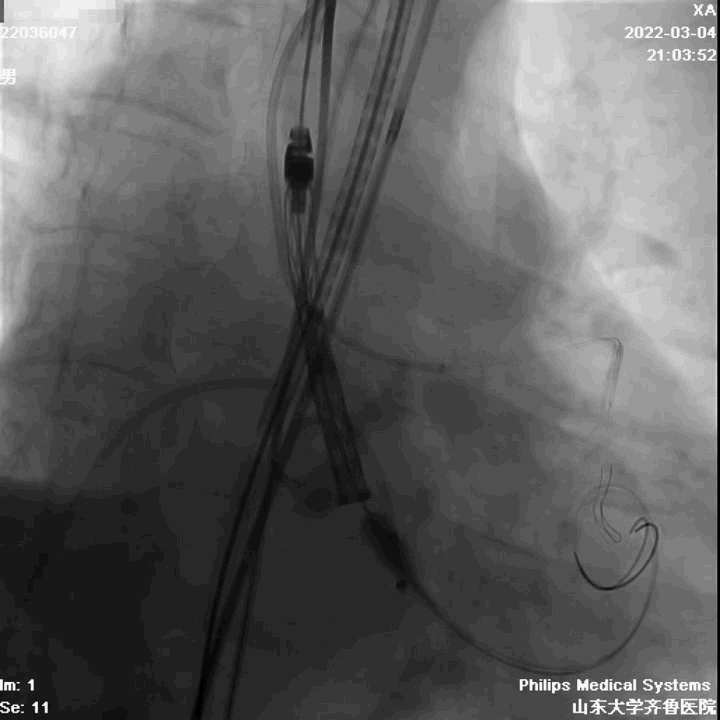

手术过程

左冠造影

右冠造影

主动脉根部造影

球囊扩张

左冠球囊保护

定位

起始缓慢释放

造影观察

瓣膜工作,造影观察

完全释放

造影

球囊后扩

最终结果

术中评估球囊扩张效果,放弃已经预装载TAV30瓣膜,植入TAV27型号瓣膜,压差由81mmHg降至5mmHg,EF由38%升至61%。